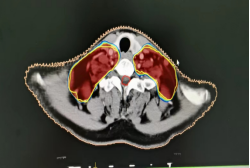

2、咽部肿瘤横断面及矢状面治疗剂量显示图